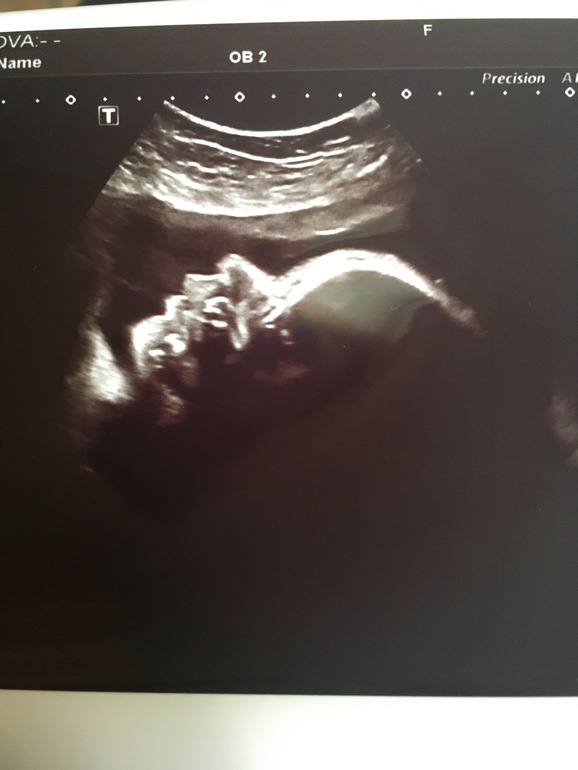

Малыш развивается согласно сроку (31 неделька)

весит уже 1600 гр (в 26 был вес 800 г).

Лежит как и положено - головой вниз

ЧСС -146.

БПР - 79 мм

ОГ - 296 мм

ОЖ - 263 мм

ДБ - 58 мм.

Плацента - 38 мм (мне кажется многовато, хотя написано норма)

Воды чистые и в нормальном количестве.

Шейка - 39 мм

Кровотоки в норме.

И вот что меня расстроило - низкая плацентация (над зевом всего 3 см - а это значит, что она не поднялась ни на мм за 2,5 месяца).